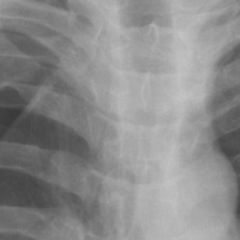

Lymphadenopathie

Der Begriff Lymphadenopathie bezeichnet eine nicht näher charakterisierte Erkrankung der Lymphknoten, beispielsweise eine Lymphadenitis oder Lymphadenose.

Eine Lymphadenopathie ist in der Regel mit einer Lymphknotenschwellung verbunden, sie kann sich aber auch durch eine veränderte Konsistenz der Lymphknoten ausdrücken. "Lymphknotenschwellung" und "Lymphadenopathie" werden dennoch im klinischen Sprachgebrauch häufig synonym verwendet.